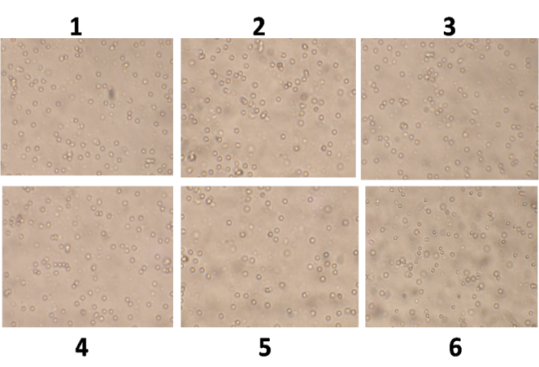

Morphological analysis

Cells were plated at 2×105 cells/well in a 6 well plate under the standard culture conditions as described above. The day after initial seeding, cells were treated with ethanol (0.01% v/v) which serve as a control and also with different doses of kaempferol (5, 10, 25, 50, 100 and 150 μg/ml) or doxorubicin alone (5, 10, 25 and 50 μg/ml) or cisplatin alone (5, 10, 25 and 50 μg/ml). After 24 h of these treatments, morphological alterations in cells were observed with phase contrast microscopy and photomicrographs were taken.

The growth of cancer cells was inhibited in a dose-dependent manner after exposure to the phytochemical (fig. 1, 2), whereas normal human lymphocytes were not affected after exposure (fig. 3). The effect of flavonoid kaempferol on the proliferation of two cancer cell lines (HCT-15 and MDA MB 231) and normal lymphocytes were determined using MTT assay. The IC50 values for kaempferol on HCT-15 and MDA MB 231 were evaluated as 120±3.2 µg/ml and 64±1.2 µg/ml respectively (table 1). When the activity of kaempferol against cancer cells was compared with that against normal lymphocytes it was evident that kaempferol had specific anti-proliferative activity against the two cancer cell lines tested (fig. 4). Further studies were performed based on the IC50 concentrations.

Fig. 1: Effect of phytochemical (kaempferol) on HCT-15, cells treated with concentrations. (1) Control; (2) 10 µg/ml; (3) 25 µg/ml; (4) 50 µg/ml: (5) 100 µg/ml and (6) 150 µg/ml. Cells were visualized under phase contrast inverted microscope (Magnification X40)

Fig. 2: Effect of phytochemical (kaempferol) on MDA MB 231, cells treated with concentrations. (1) control; (2) 5 µg/ml; (3) 10 µg/ml; (4) 25 µg/ml; (5) 50 µg/ml; (6) 100 µg/ml. Cells were visualized under phase contrast inverted microscope (Magnification X40)

Fig. 3: Effect of phytochemical (kaempferol) on lymphocytes, cells treated with concentrations. (1) control; (2) 5 µg/ml; (3) 10 µg/ml; (4) 25 µg/ml; (5) 50 µg/ml; (6) 100 µg/ml; Cells were visualized under phase contrast inverted microscope (Magnification X40)